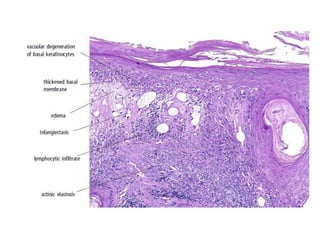

HISTOPATHOLOGY